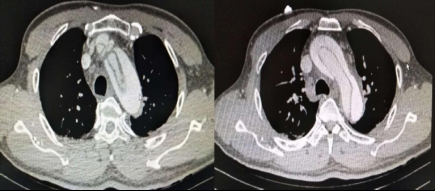

患者于当日23:50送达本院急诊抢救室。来院时神志不清,GCS评分7分,血压132/87 mmHg(1 mmHg=0.133 kPa),心率90次/min,呼吸22次/min,脉搏92次/min,血氧饱和度96%,血糖6.7 mmol/L。查体见面色红润,舌体咬破。两肺呼吸音清,未闻及干湿性啰音,心律齐,无明显病理性杂音,腹平软,压痛反跳痛难以配合,两侧病理征未引出。2019-01-02 23:58心电图示窦性心律,ST段改变(图 1A)。2 h后复查心电图示窦性心动过缓,ST-T改变,左室高电压、心电轴左偏,Ⅰ、Ⅴ5、Ⅴ6导联ST段呈水平型、下斜型压低,0.05~0.1 mV,Ⅴ1、Ⅴ2、AVR呈水平型抬高(图 1B)。(2019-01-03 00:15)床边检测cTnT 0.014 ng/mL,D-二聚体 > 10 000 ng/mL,NT-pro BNP 20 600 ng/L。2 h后复查cTnI 0.049 ng/mL。生化示肌酐284 μmol/L,其余指标未见明显异常。头颅CT示右侧颞枕叶条片灶,局部似与右侧脑室后角相连,脑裂畸形:合并灰质异位?软化灶合并脑穿通畸形?(图 2)。胸部CT示心脏增大、肺动脉高压,肺动脉主干增宽4.0 cm,心包前部少许积液。床边心超示:左室壁运动欠协调,室间隔运动稍减弱,主动脉瓣反流(轻度),EF为52%。患者入院后烦躁不安,先后予镇静、抗癫痫等治疗。因患者D-二聚体升高明显,胸部CT示肺动脉增宽明显、肺动脉高压,考虑存在肺栓塞可能; 另一方面,患者血压呈进行性上升,D-二聚体升高,CT示心包前部少许积液,故主动脉夹层亦不能除外,需行动脉造影明确,但因患者肌酐异常,存在慢性肾衰竭,行增强CT检查需注射造影剂,可能进一步加重肾损害,故家属拒绝。2019-01-03 07:00患者神志转清,诉有头晕,无胸痛,血压持续波动在200/100 mmHg左右,予镇静、降压效果均较差,病情反复告知家属,家属商议后最终同意行CTA检查。13:05行胸部增强+肺CTA示主动脉弓夹层(De Bakey I、Stanford A型),肺动脉高压(图 3)。最终患者诊断主动脉夹层(De Bakey I、Stanford A型)明确,因本院手术条件所限,当天即予转上一级医院手术治疗。

| 图 3 患者肺CTA示主动脉弓夹层(Stanford A型) |